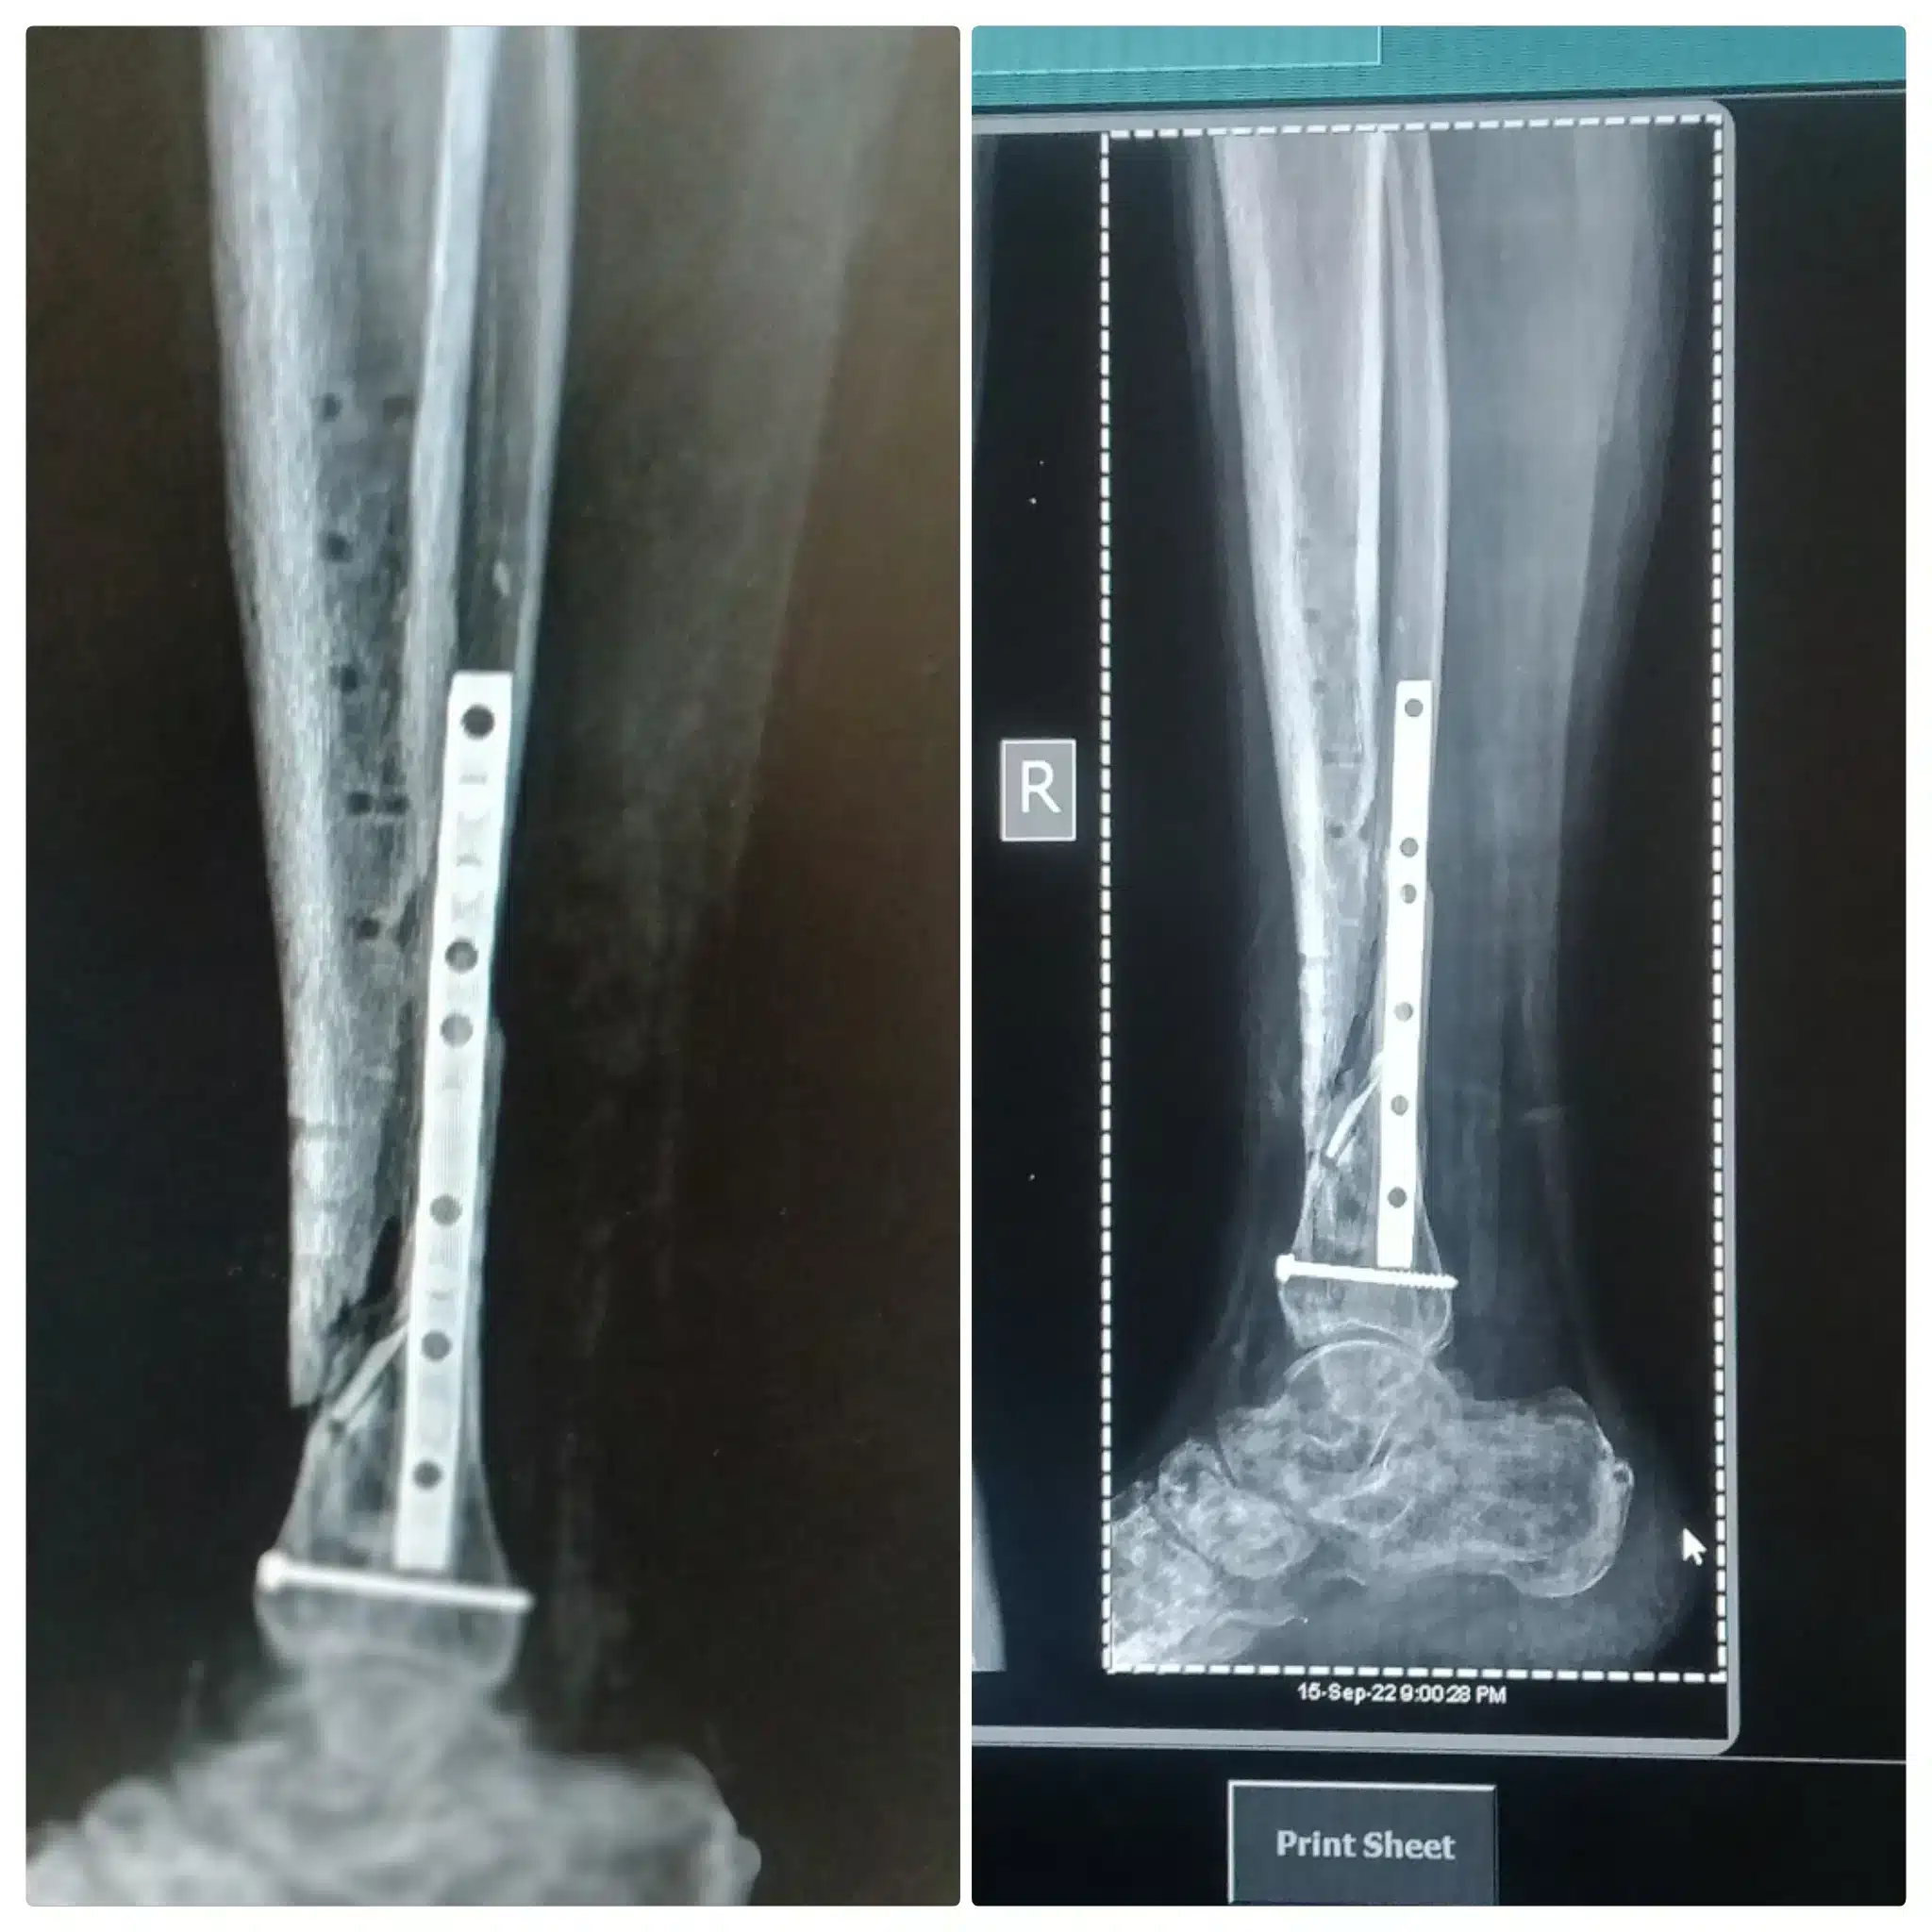

عملية تركيب شريحة ومسامير في الفخذ من الإجراءات العلاجية التي يلجأ لها الأطباء في حالة تعرض عظام الفخذ للإصابات أو كسور شديدة، وهي تتم عن طريق عدة خطوات، ومنها:

- يقوم بتطعيم الفراغ الموجود بين العظام وتركيب شريحة ومسامير والتأكد من ثبات جميع الأجزاء في مكانها.